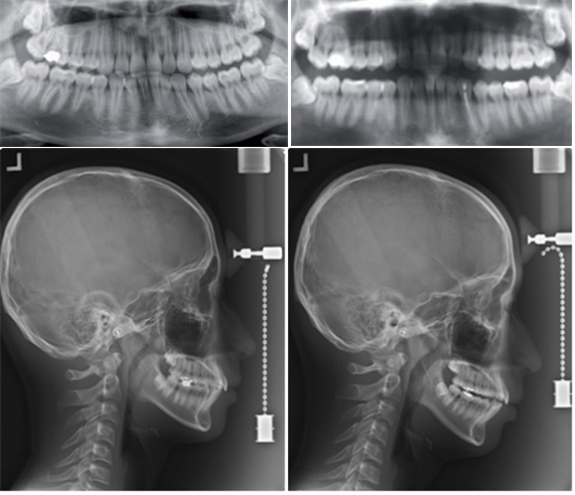

(사진제공: 대한치과의사협회)

협회에 따르면, 일부 온라인 쇼핑몰에서 치과의사의 진단 없이 마우스피스가 판매되고 있다. 그러나 해당 장치로 인해 △치아나 잇몸의 손상 △부정교합 △턱관절 장애 유발 △파손 또는 파절로 인한 기도 흡입 등 다양한 부작용 유발 사례가 속출하고 있다.

학회는 “치아의 파절, 치아의 괴사, 치관 파절, 치근 파절, 치아 발거, 잇몸 및 연조직의 외상과 궤양, 치조골의 상실, 보철물의 탈락 등 다양한 부작용이 발생할 수 있는 것으로 보고된 바 있다”며 “전문가인 치과의사에 의한 진단 및 치료 계획의 부재와 더불어, 교정 진행 과정에서 필요한 관찰과 치료 계획의 변경도 불가능해 소비자의 피해를 최소화할 수 있는 최후의 기회마저 박탈될 수 있다”고 우려를 표했다.